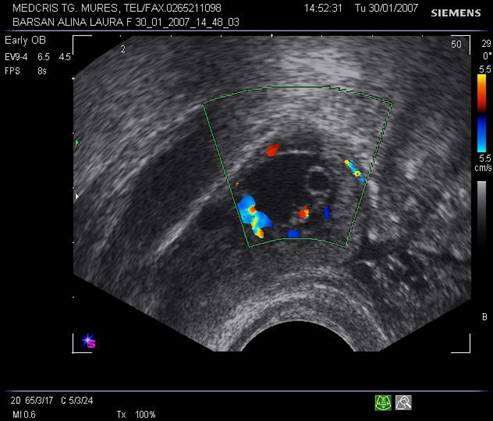

Fig nr 53 Aceeasi sarcina extrauterina ca in figura precedenta, se evidentiaza coroana trofoblastica la ecoul doppler color si se schiteaza vezicula vitelina ( cu sageata )